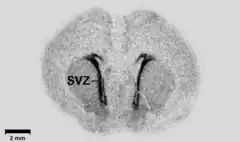

In biology, this technique may be used to determine the tissue (or cell) localization of a radioactive substance, either introduced into a metabolic pathway, bound to a receptor[4][5] or enzyme, or hybridized to a nucleic acid.[6] Applications for autoradiography are broad, ranging from biomedical to environmental sciences to industry.

The use of radiolabeled ligands to determine the tissue distributions of receptors is termed either in vivo or in vitro receptor autoradiography if the ligand is administered into the circulation (with subsequent tissue removal and sectioning) or applied to the tissue sections, respectively.[7] Once the receptor density is known, in vitro autoradiography can also be used to determine the anatomical distribution and affinity of a radiolabeled drug towards the receptor. For in vitro autoradiography, radioligand was directly applying on frozen tissue sections without administration to the subject. Thus it cannot follow the distribution, metabolism and degradation situation completely in the living body. But because target in the cryosections is widely exposed and can direct contact with radioligand, in vitro autoradiography is still a quick and easy method to screen drug candidates, PET and SPECT ligands. The ligands are generally labeled with 3H (tritium), 18F (fluorine), 11C (carbon) or 125I (radioiodine). Compare to in vitro, ex vivo autoradiography were performed after administration of radioligand in the body, which can decrease the artifacts and are closer to the inner environment.